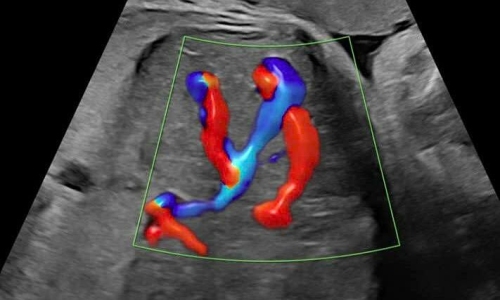

Rare fetal hepatic vascular malformation detected VnExpress Doctors closely monitored a pregnancy after detecting a fetal hepatic vascular malformation, choosing the optimal time for intervention, which resulted in a healthy birth at 39 weeks.